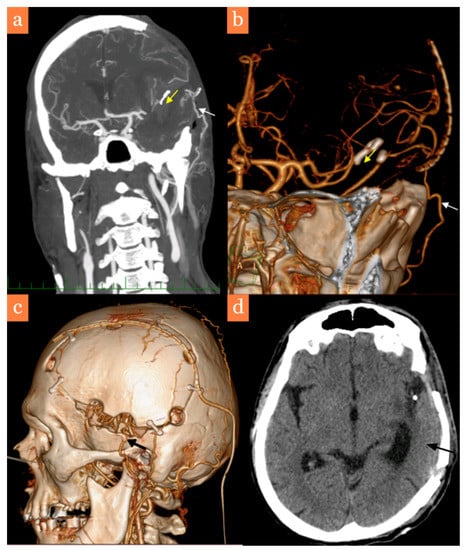

2. Case Report